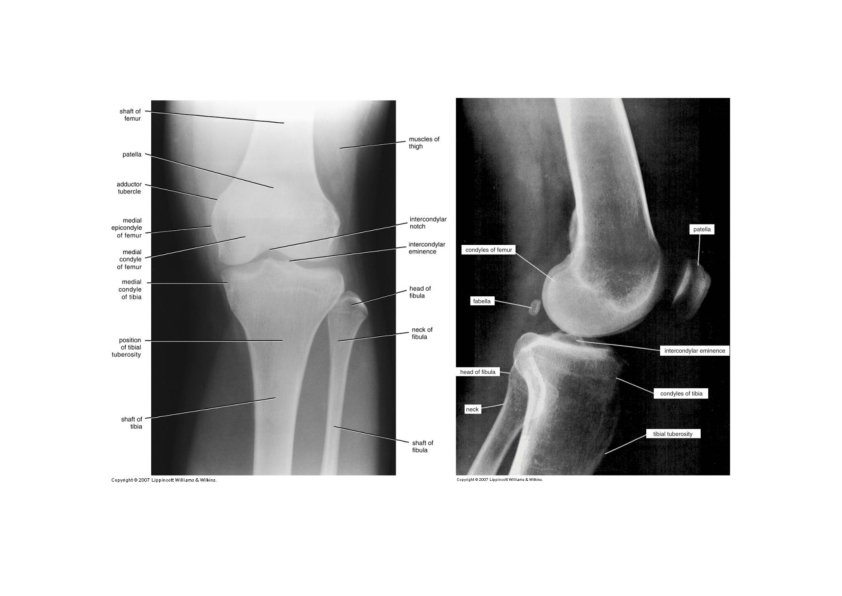

Femur (thighbone) • longest & strongest bone in body • head articulates with acetabulum (attached by ligament of head of femur) • Fovea capitis • neck is common fracture site • greater & lesser trochanters, linea aspera, & gluteal tuberosity-- muscle attachments • Adductor tubercle - - adductor magnus • medial & lateral condyles articulate with tibia • patellar surface anteriorly between condyles • intercondylar fossa - depression between the condyles • Angle of inclination • Normal range 115°- 140° • Male > Female

Patella • Largest sesamoid bone in the body • Forms the patellofemoral joint • Superior surface is the base • Inferior, narrower surface is the apex • Thick articular cartilage lines the posterior surface • Increases the leverage of the quadriceps femoris muscle

Surface Anatomy of Femur • Greater trochanter • Femoral epicondyles • Adductor tubercle • Patella

Tibia and Fibula • Tibia • medial & larger bone of leg • weight‐bearing bone • lateral & medial condyles • Intercondylar …… • tibial tuberosity for patellar lig. • proximal tibiofibular joint • medial malleolus at ankle • fibular notch • Fibula • not part of knee joint • muscle attachment only • Head, neck, shaft • lateral malleolus at ankle